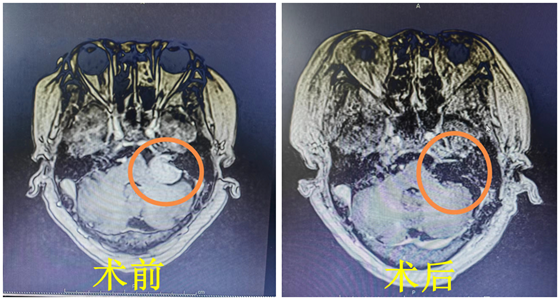

患者术前、术后影像对比图

近日,湘雅常德医院神经外科袁贤瑞教授团队为一位身患13种基础疾病的七旬老人成功实施颅内病灶切除术+脑脊液瘘修补术,切除了3厘米大小的脑膜瘤,同时三叉神经、面神经、蜗神经、后组颅神经及岩静脉等保留完好。术后患者恢复良好,择日出院。

手术如期进行,在全麻下行颅内病灶切除术+脑脊液瘘修补术。术中分离肿瘤与周围血管、脑组织的粘连是一项巨大的挑战,在显微镜下,袁贤瑞教授带领的团队默契配合,犹如艺术家般精雕细琢,逐步将肿瘤与重要结构分离后切除,经过约6小时抽丝剥茧般的手术,最终手术取得如预期一样的成功,位于华阿姨脑部直径约3*3*2.5厘米的肿瘤完整切除,同时三叉神经、面神经、蜗神经、后组颅神经及岩静脉等保留完好。